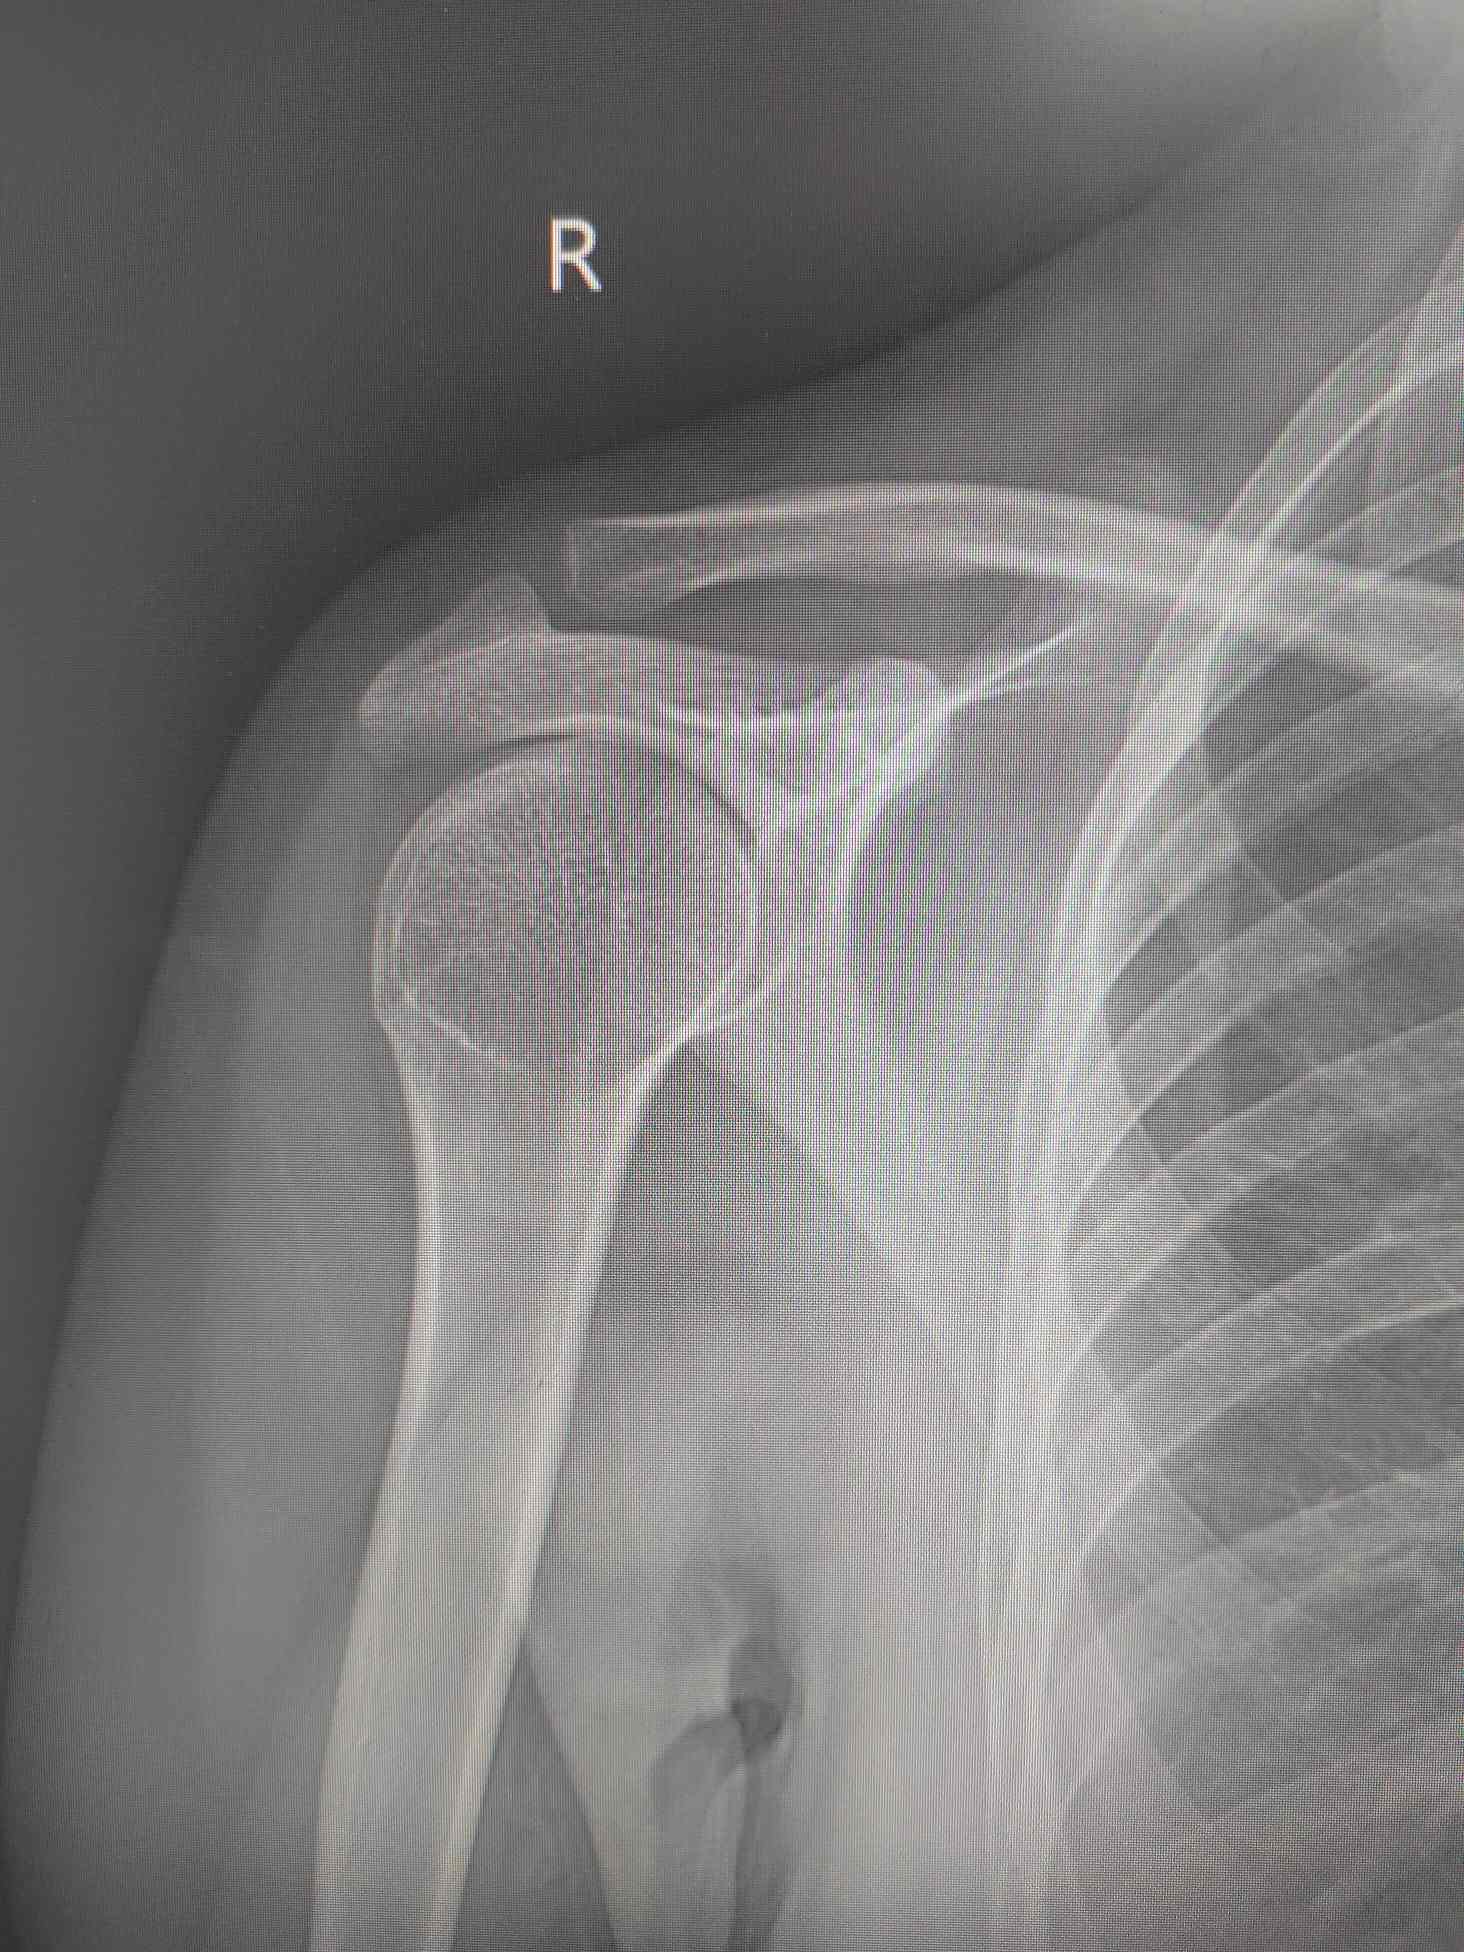

“方肩畸形”、“弹性固定”、“杜加实验阳性”……经过认真查体,确诊为“右肩关节脱位”,但考虑到小王经受了三番五次的非麻醉下复位,薛继强医师并没有立即为其复位,而是建议再次拍片排除先前多次复位可能造成的医源性骨折。再次拍片排除骨折之后,薛继强医师根据小王的描述,大致了解之前几位医生所用的复位方法,为了避免重蹈覆辙,薛继强医师采用俯卧位悬吊牵引结合推肩胛骨复位法,成功为小王复位。小王非常感激,“真是妙手回春,洛阳正骨果然名不虚传……”妥善固定后拍片确认复位成功,薛继强医师交代好注意事项,小王决定继续留在洛阳游玩。